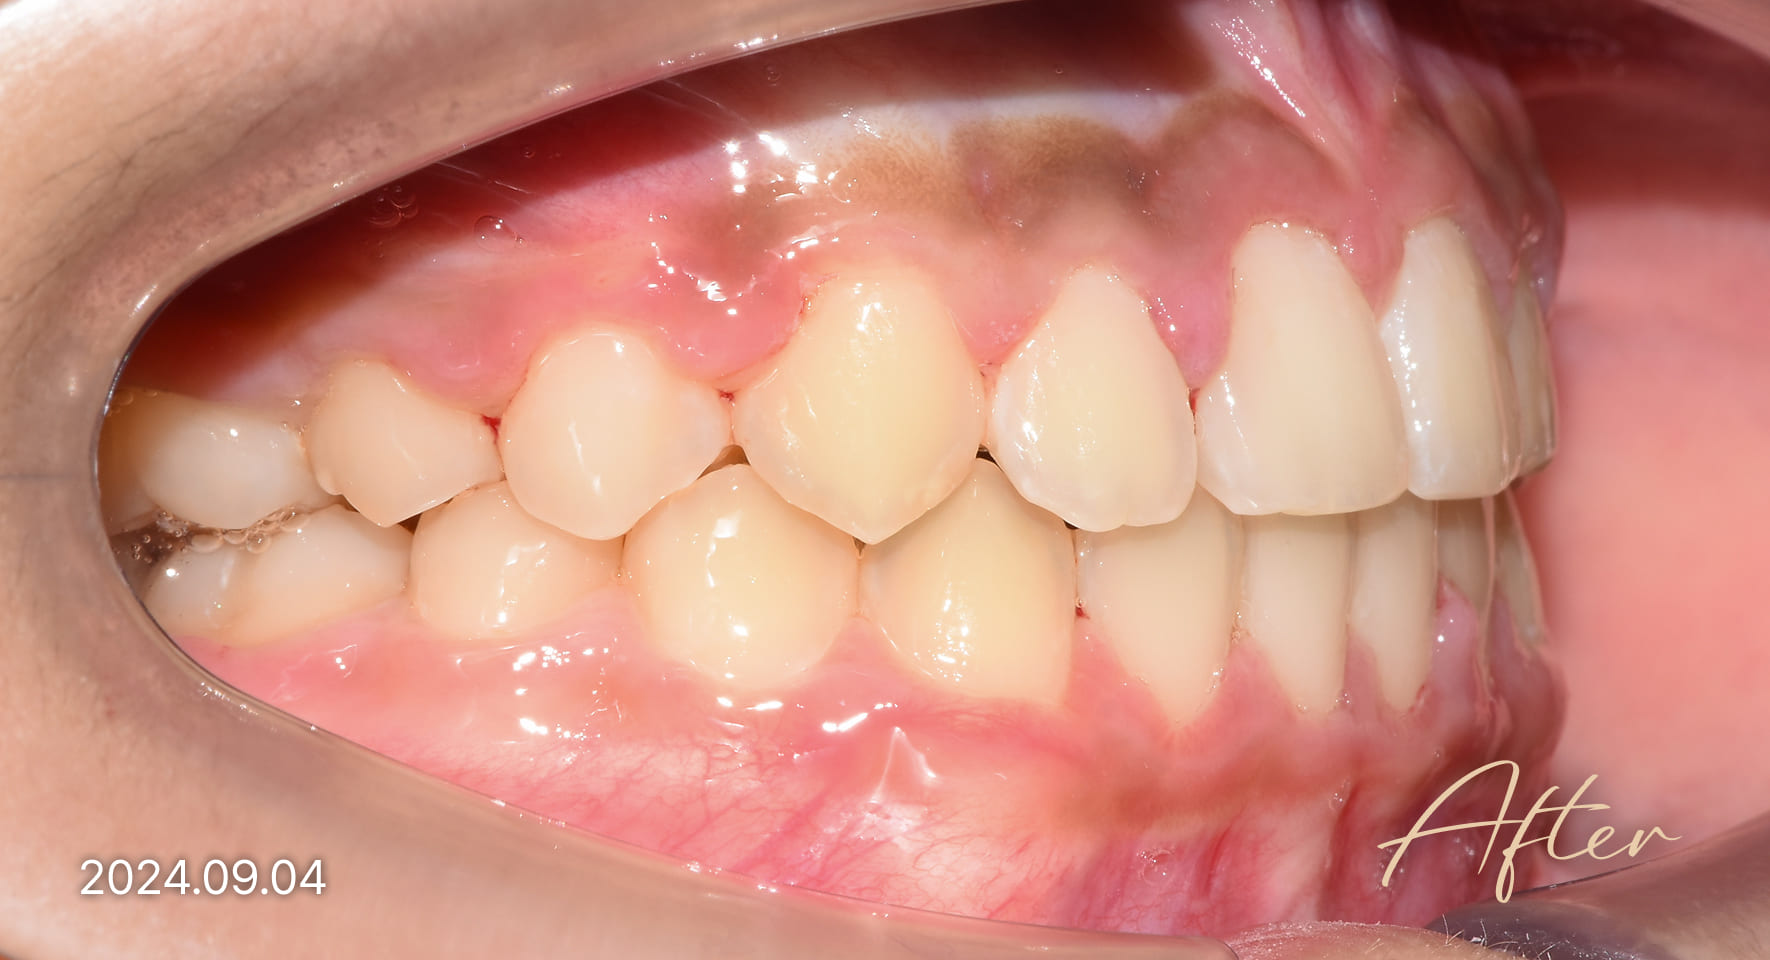

성장기 교정 치료사례

본 사진은 진심을담은치과교정과 치과의원에서

치료한 환자의 동일 인물 전·후 사진입니다.

개인의 구강 상태 및 관리 방법에 따라 통증 및 잇몸 염증,

턱관절 불편감 등의 부작용이 발생할 수 있습니다.

치료 전 치료 후